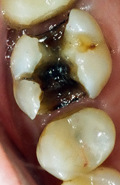

Um Riesenlöcher (Karies) in den Zähnen zu vermeiden (Abb. 7), geben wir Ihnen auch eine umfassende Information über Ernährung. Wir erklären Ihnen die Zusammenhänge, wann der Genuss von Süssigkeiten für Ihre Zähne verheerende Folgen haben kann und unter welchen Umständen überhaupt keine Zahnschäden entstehen müssen. Ist eine Karies allerdings einmal vorhanden, muss sie unbedingt behandelt werden. Wie, das erklären wir Ihnen gerne im Kapitel Allgemeine Zahnmedizin.